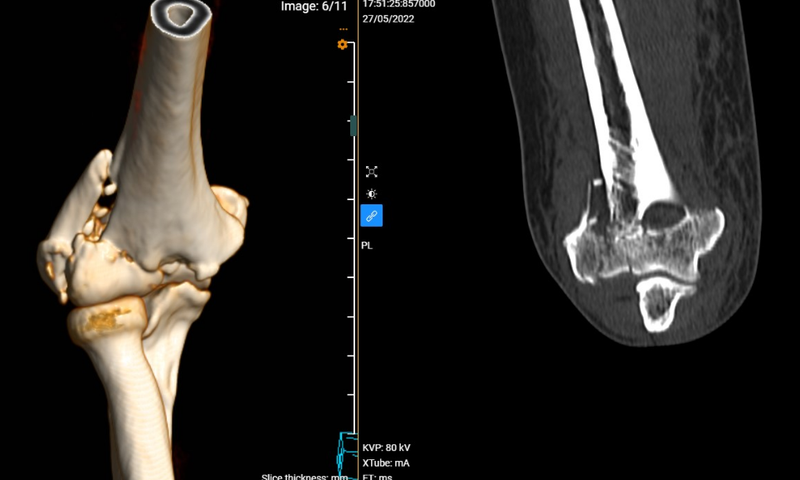

Gãy chỏm xương quay là dạng chấn thương phổ biến, chiếm 1 - 4% tất cả trường hợp gãy xương ở người lớn, chiếm khoảng 20% tất cả các chấn thương vùng khuỷu. Nhiều trường hợp trật khớp khuỷu có kèm theo gãy chỏm quay. Vậy gãy chỏm xương quay là tình trạng gì? Nguyên nhân nào gây bệnh?

Chỏm quay là một loại khớp độc lập giữ nhiệm vụ quan trọng ở khuỷu tay. Chức năng của khớp này là quay xung quanh xương trụ, nhờ đó khuỷu tay có thể xoay, lật sấp ngửa, co duỗi, đồng thời chịu lực của tay. Khi một người ngã chống tay tư thế duỗi khuỷu sẽ xảy ra tình trạng gãy chỏm xương quay. Đây là tình trạng nghiêm trọng, khiến bệnh nhân cử động khó khăn và bệnh nhân có thể đối mặt nhiều biến chứng nguy hiểm.

Gãy chỏm xương quay là chấn thương phổ biến nhất ở vùng khuỷu tay, thường gặp ở cả trẻ em và người lớn, thường gặp ở nữ giới hơn nam giới và gặp nhiều ở người từ 30 - 40 tuổi.

Dạng chấn thương này chiếm tỷ lệ khoảng 1/3 trong số các dạng gãy xương hay khớp ở vùng khuỷu tay và thường liên quan tới các chấn thương khác như tổn thương dây chằng, trật khớp ở khuỷu, gãy mỏm vẹt,...

Có 4 mức độ gãy chỏm xương quay từ nhẹ tới nặng như sau:

Gãy xương loại III, IV

Trường hợp gãy nát chỏm quay thành nhiều mảnh gọi là gãy xương loại III. Khi bị gãy đầu quay loại III, khớp khuỷu tay và dây chằng bao lấy khuỷu tay cũng bị tổn thương nghiêm trọng.

Với trường hợp này, bác sĩ thường chỉ định phẫu thuật để loại bỏ hoặc cố định các mảnh xương gãy và sửa chữa tổn thương ở mô mềm. Nếu tình trạng gãy nát nhiều mảnh, bác sĩ có thể sẽ phẫu thuật lấy bỏ chỏm quay. Với những trường hợp này, để cải thiện chức năng lâu dài, có thể thay chỏm quay nhân tạo.